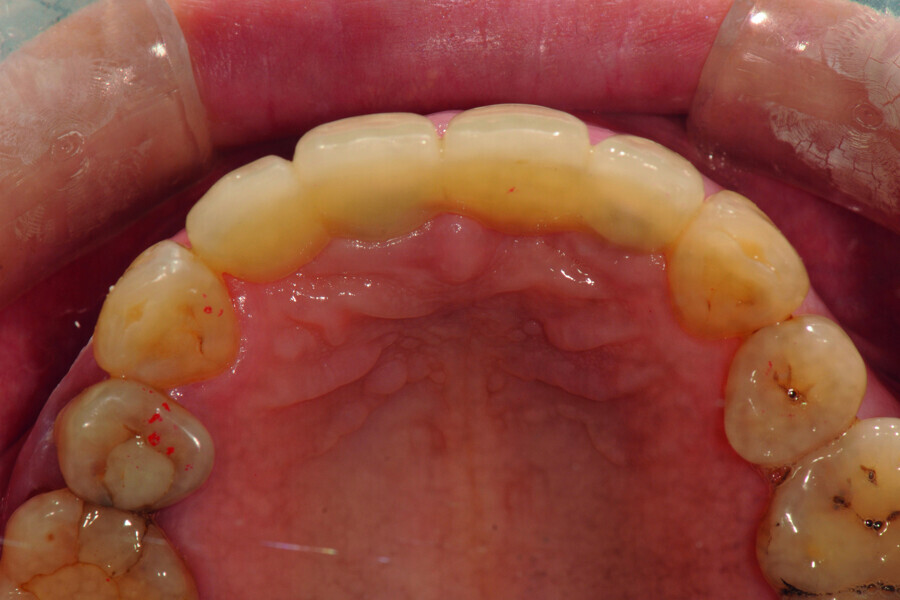

Fig. 8: Occlusal view of the anterior teeth three months post-op.